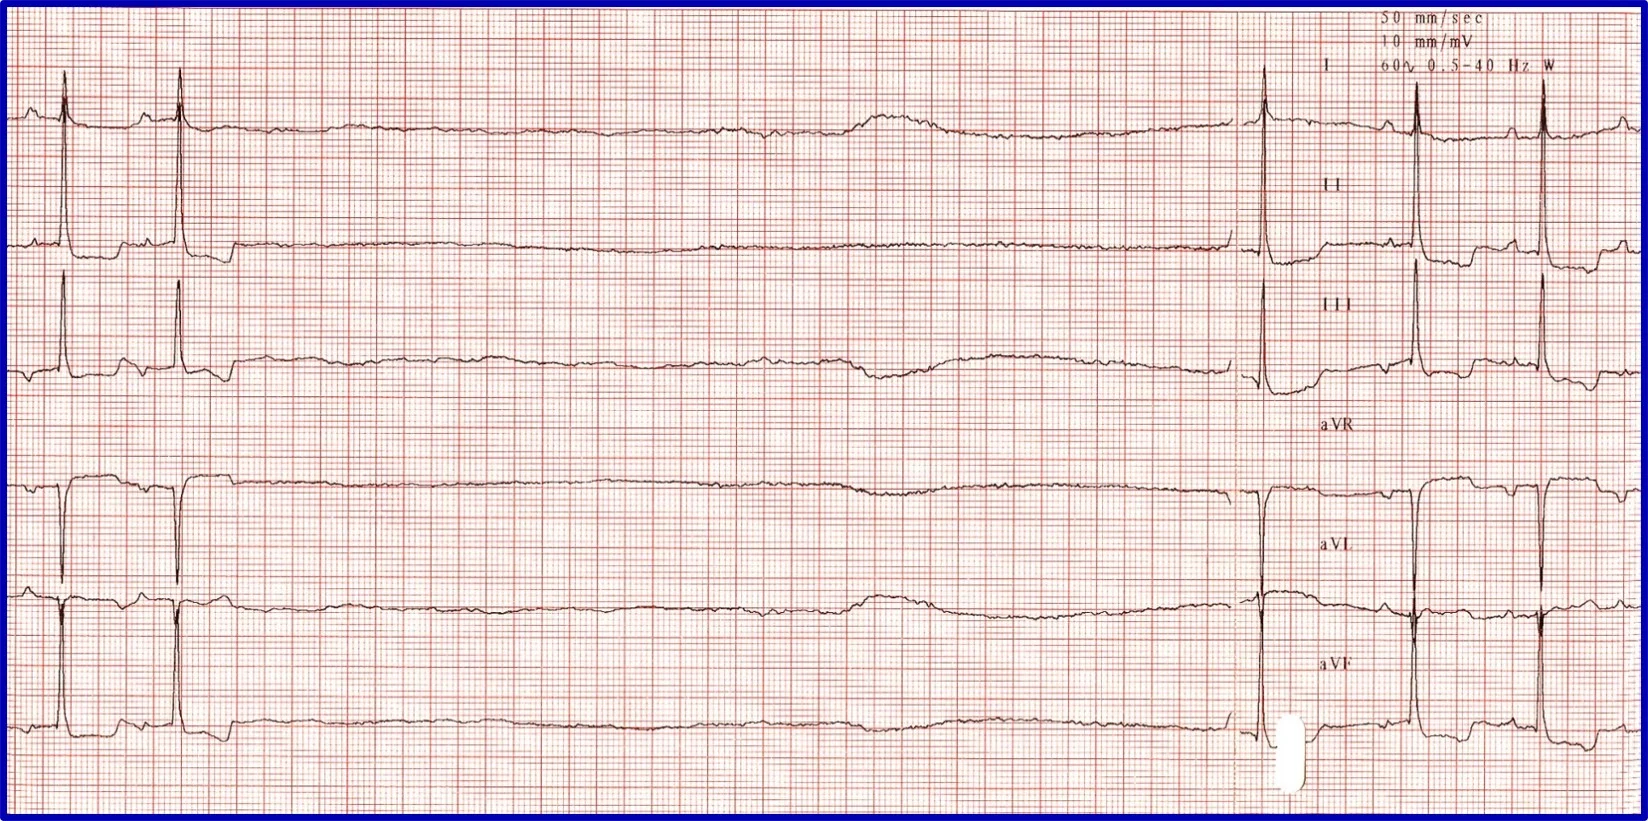

Sick sinus syndrome (SSS)/sinus node dysfunction (SND) is a conduction disease of the SA node believed to be degenerative. Other regions of the conduction system may also be diseased. Escape rhythms do not always, therefore, appropriately rescue the rhythm. ECG features of SSS/SND include sinus arrest (ie, cessation of SA node activity/no atrial activity or P waves identified and absence or delay of expected escape/rescue rhythms from other automatic tissues in the heart [eg, bundle of His, Purkinje fibers, ventricular tissue]; Figure 8). For example, the intrinsic rate of the AV node is 40 to 60 bpm. If the SA node pauses >1.2 seconds, the AV junction should depolarize and produce a junctional beat. Likewise, if the SA node (intrinsic rate, 30 bpm) pauses for >2 seconds, the Purkinje fibers should fire and rescue the rhythm; however, this often does not occur or is inappropriately delayed in patients with SSS/SND, and sinus arrest/asystole can last for several seconds. Junctional rhythms may become the dominant rhythm. Administration of a high-end dose of atropine (0.04 mg/kg SC or IM) may result in an increase in heart rate. Lack of an appropriate response (ie, AV block resolves, sinus rate increases to >180 bpm, every P wave is associated with a QRS complex, PR intervals are constant) is diagnostic for SSS/SND; however, a partial or even complete response does not necessarily rule out SSS/SND. SSS/SND is highly influenced by autonomic tone; therefore, a partial or full response to atropine in a breed predisposed to SSS/SND (eg, West Highland white terriers, schnauzers, dachshunds, cocker spaniels) with clinical signs and ECG or Holter characteristics of SSS/SND does not exclude this diagnosis.

(A) ECG in a patient with SSS/SND and a delay of escape focus to rescue the rhythm. (B) Thirty minutes after administration of atropine (0.04 mg/kg IM), ECG showed resolution of SSS/SND, but the SA node was only able to speed up to 140 bpm, indicating that although the dysfunction was heavily influenced by autonomic tone, there was an incomplete response to obliterating vagal tone. The SA node was not able to operate at full function.